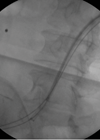

In the sixth article in this series the authors describe endourology nightmares involving ileal conduits and calculi. Case 1 A 69-year-old man who had a cystectomy and ileal conduit for muscle invasive bladder cancer, presented with an acute kidney injury...